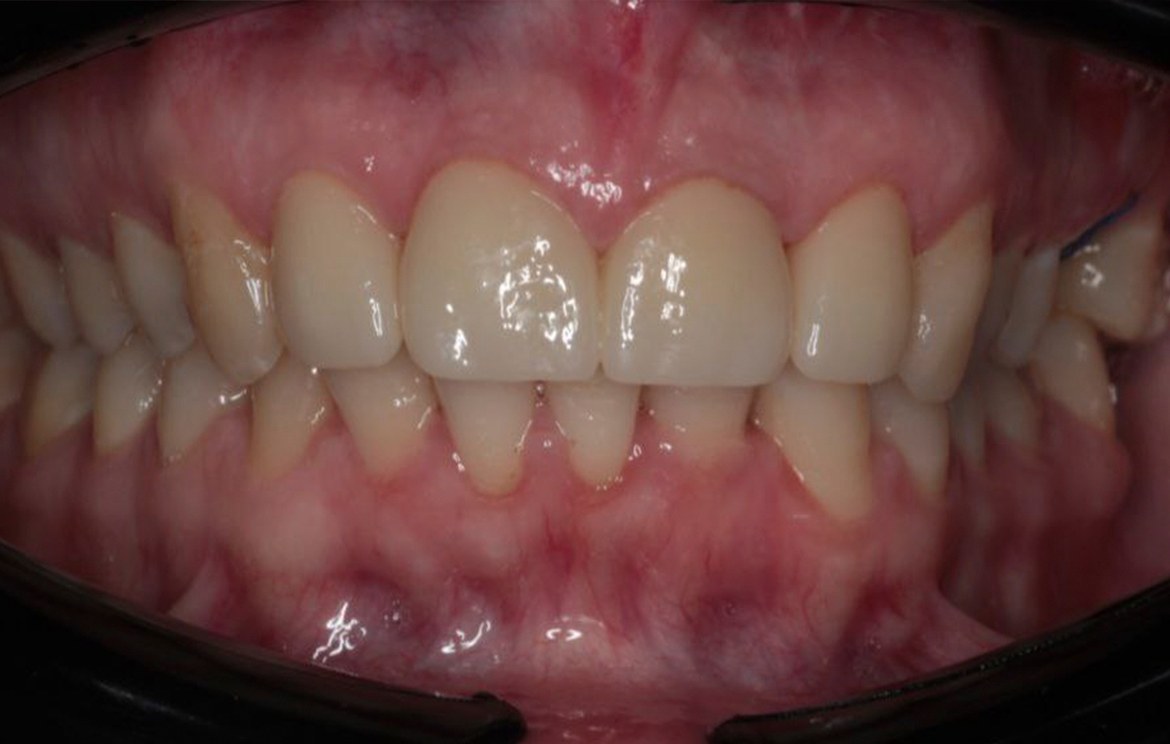

Наши работы